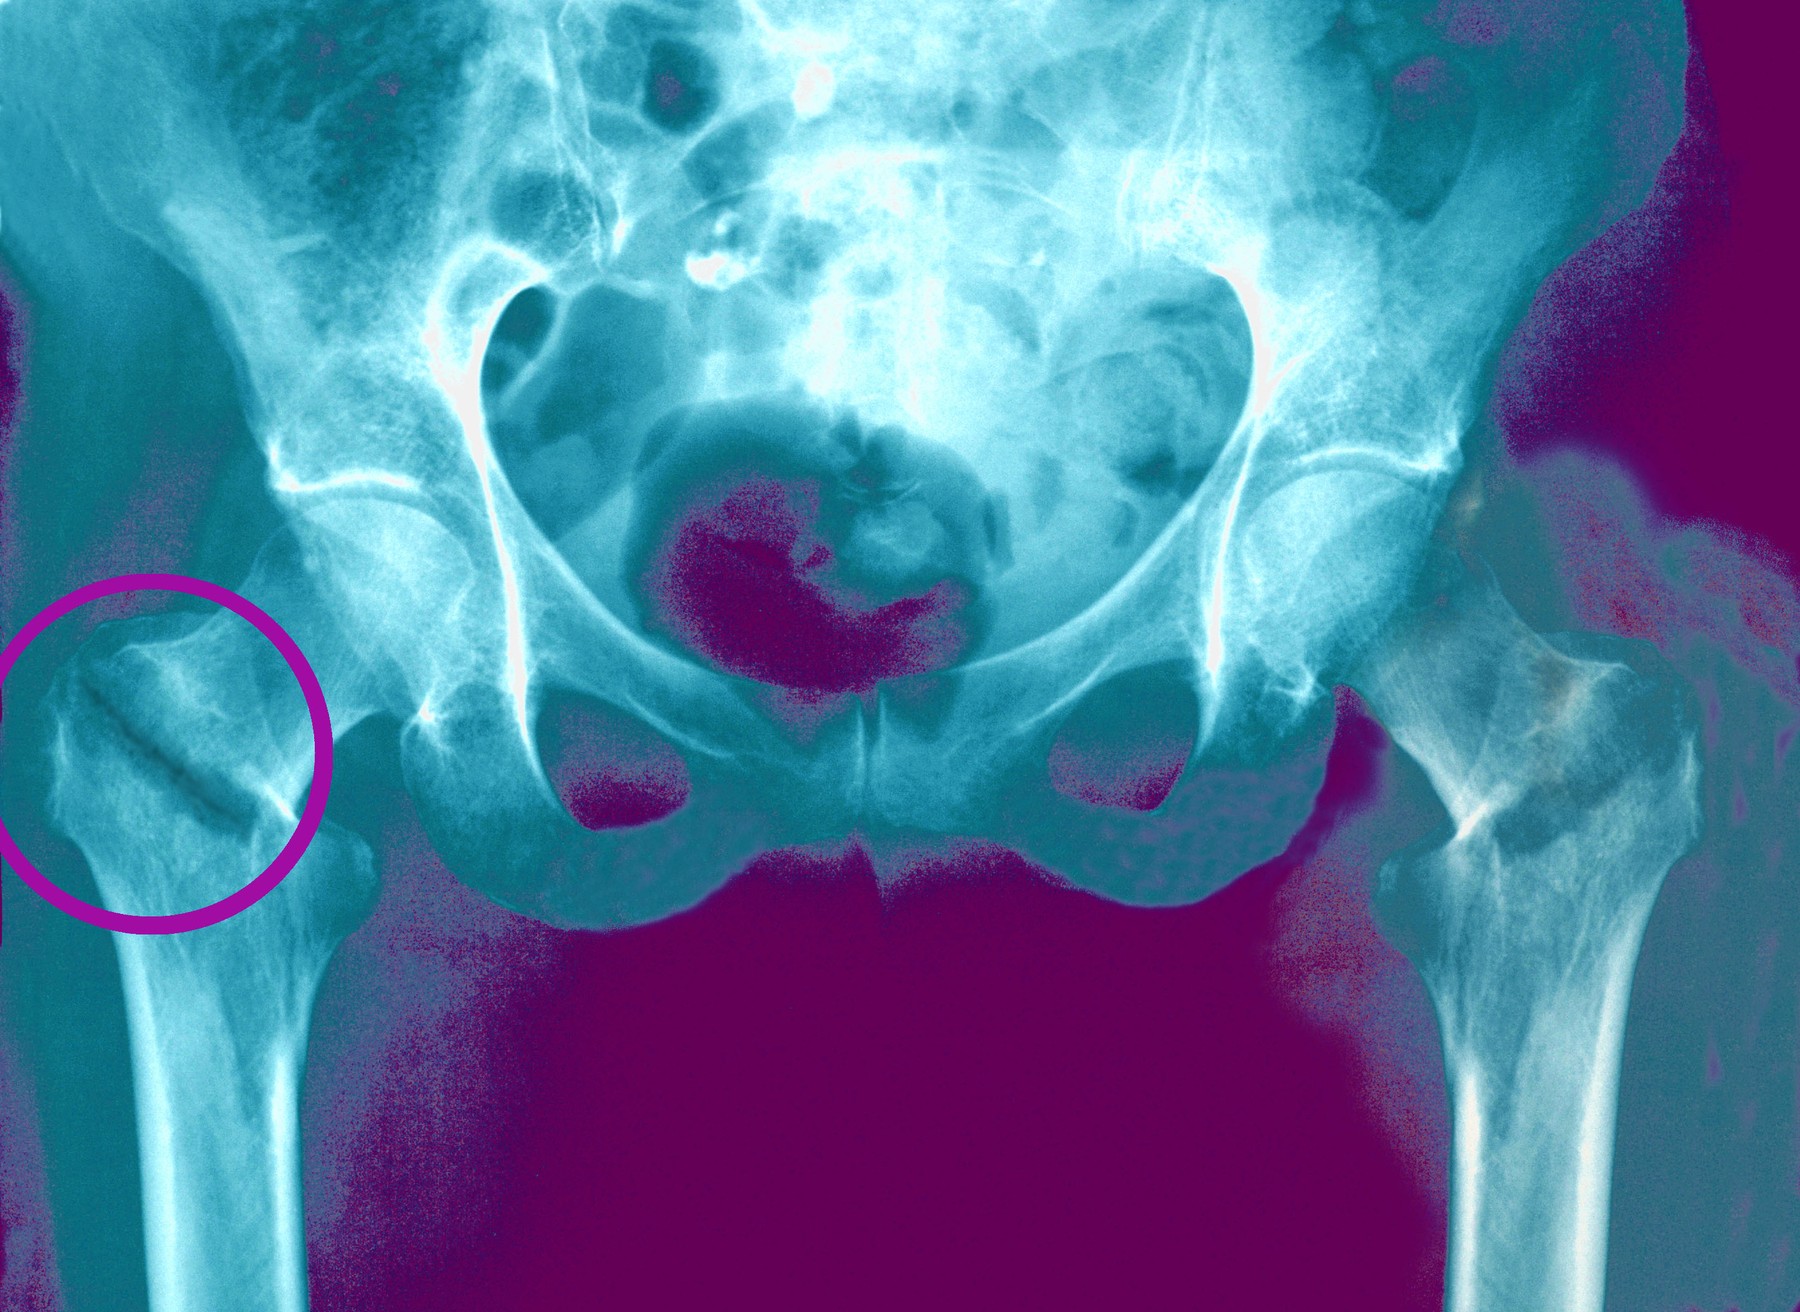

Raziskovalci so analizirali podatke 163.855 udeležencev s povprečno starostjo 56 let. Udeležence so spremljali približno 12 let. V tem obdobju so zabeležili 1.097 zlomov kolka in 7.889 vseh zlomov.

Rezultati so pokazali, da je bil višji vnos ultrapredelane hrane povezan z nižjo kostno mineralno gostoto na več delih okostja. Pri udeležencih, ki so pojedli največ predelane hrane, so raziskovalci ugotovili nižjo gostoto kosti stegnenice, ledvenega dela hrbtenice ter na ravni celotnega telesa.

Raziskava je pokazala, da je bil višji vnos ultrapredelane hrane povezan z večjim tveganjem za zlome. Pri ljudeh z opazno višjim vnosom takšne hrane je bilo tveganje za zlom kolka približno deset odstotkov večje, za vse zlome skupaj pa 2,7 odstotka večje.